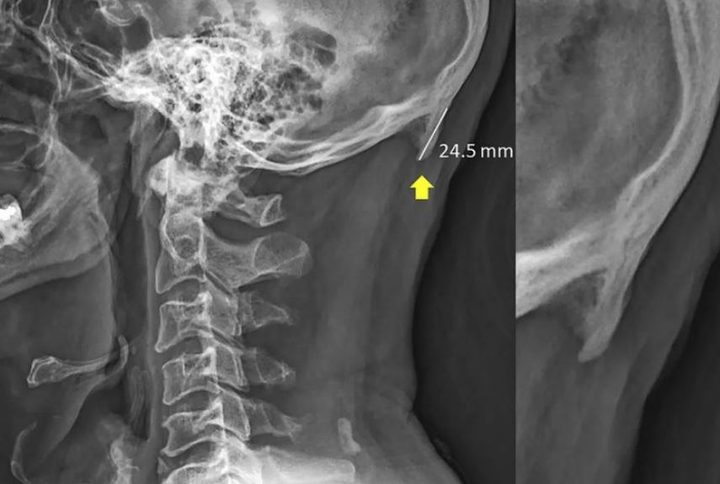

Investigadores de la Universidad Sunshine Coast en Queensland, Australia, han encontrado recientemente un crecimiento óseo en la base de los cuellos de los adultos jóvenes, que parece un cuerno que sobresale del cráneo. Según informa el Washington Post, los expertos atribuyen este nuevo crecimiento a la flexión consistente de la cabeza al usar teléfonos inteligentes o dispositivos de mano.

El trabajo de investigación analizó 218 radiografías de adultos jóvenes de 18 a 30 años y encontró que el 41 por ciento tenía un crecimiento óseo. Según el estudio, los hombres presentaban una prominencia más notable que las mujeres. El tamaño de estas protuberancias sugiere que tardaron mucho tiempo en desarrollarse, muy probablemente desde la infancia, por lo que si bien el uso de teléfonos inteligentes podría ser un factor vinculado, los investigadores dicen que podría no ser el único.